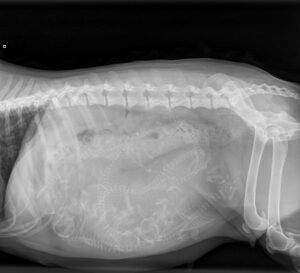

Aster went to the vet today for a pregnancy count x-ray. The vet clearly saw 6 puppies, and said everything looked good. ChatGPT analyzed the two x-rays and counted 7 puppies. So, in a couple of days we shall see. Aster is in the final stretch.